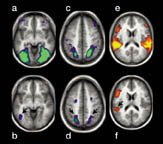

"These new studies set the stage for more intensive explorations of memory retrieval in the brain," remarks Anthony D. Wagner of the Massachusetts Institute of Technology in Cambridge."See more on Remembrance here